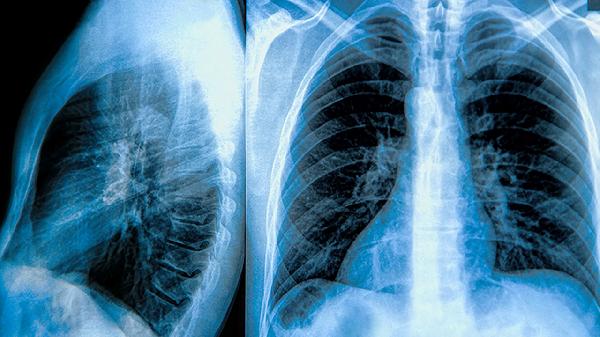

肺大泡会自己消失吗

肺大泡通常不会自行消失,需要通过医疗干预或生活调整进行改善。肺大泡的形成多与慢性阻塞性肺疾病、长期吸烟或肺部感染等因素有关,其治疗方法包括药物治疗、手术治疗和生活方式调整。

2、手术治疗:对于较大或症状严重的肺大泡,手术可能是必要的。常见的手术方式包括肺大泡切除术、胸腔镜手术和肺减容手术,这些手术旨在减少肺大泡的体积,改善肺功能。

肺大泡的治疗需要综合考虑患者的具体情况,通过药物治疗、手术治疗和生活方式调整,可以有效控制症状并改善肺功能。定期复查和遵循医生的建议是确保治疗效果的关键。